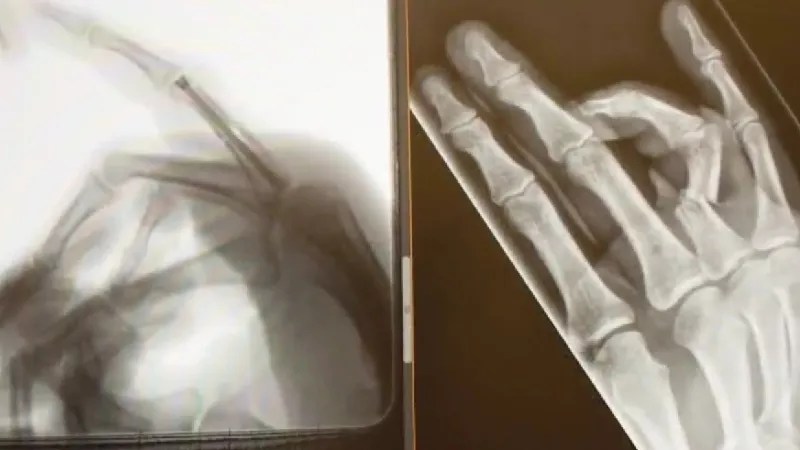

Two X-ray images of Trevor Hughes’s hand.

In some ways, Hughes was fortunate, “because if the camera hadn’t been there, the projectile would have hit him in the face,” McNulty notes. “But it severed one of the fingers on his hand and left it dangling, spurting blood everywhere.”

The severity of the wound meant Hughes needed immediate medical care. “He had to have surgery to reattach his finger,” McNulty says. “It’s held together with a screw and he’s rehabbing it to this day. And all this happened because he was part of a largely peaceful march – but officers still decided to inflict brutality on the protesters, including someone who was filming them and had no intention of doing anything wrong.”